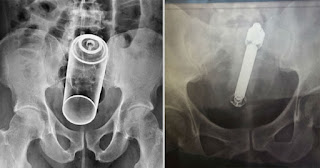

1. Μπουκάλι-σπρέι